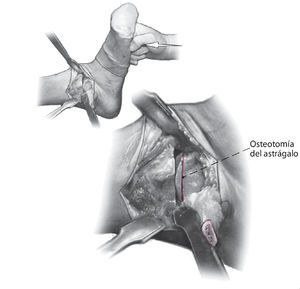

La técnica quirúrgica se ilustra en las figs. 1-13.

Fig. 7 Coloque el pie en la posición deseada usando el lado contralateral como plantilla. Plantígrado con 5-8º valgo y 5-15º de rotación externa. Cuando se haya identificado la posición deseada, se realiza una osteotomía sutil de la superficie superior del astrágalo de forma exactamente paralela a la osteotomía tibial.